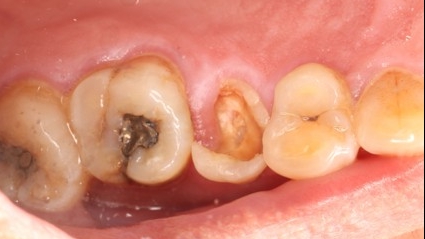

June 20, 2025: The patient's chief complaint is that endodontic treatment was performed on the right maxillary posterior tooth abroad, and a deep carious lesion has been recently detected, requiring restoration. The following are the intraoral photographs taken upon the patient's first visit: a large carious lesion is visible on the occlusal surface of tooth 15 (FDI numbering), with only the buccal wall remaining. Percussion test and cold-hot stimulation test showed no response, and yellow obturation material is visible at the root canal orifices.

Treatment Plan: Given the patient’s refusal of extraction and implant placement, conservative treatment is adopted: retreatment of the root canal followed by post-and-core restoration.